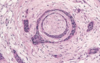

What are the aetiological agents of pemphigoid

IgG and C3 attack basement membrane

Eosinophils recruited → elastase → damages anchoring proteins → fluid fills up gap between BM and epithelium

What are the histological features of bullous pemphigoid

↑ eosinophils

How can you confirm the diagnosis of pemphigoid?

Immunofluorescence shows IgG along basement membrane

IgG anti-hemidesmosome